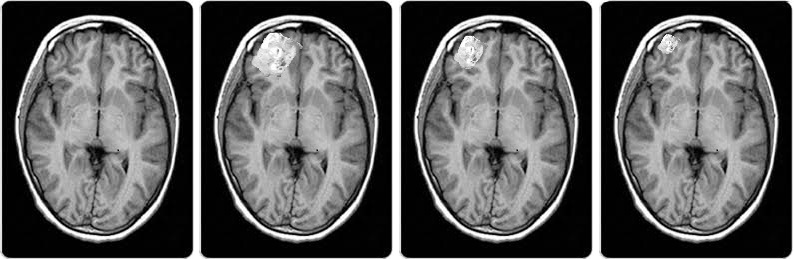

The experiment conducted by selected an appropriate high level concept. In this experiment we consider the size of the brain tumors as the high level concept. We augmented a subset of healthy images with brain tumors segmented form other images. The segmented brain tumors have been scaled into 3 different categories of large, average, and small. The purpose of the experiment is to determine the impact of the tumor size on the classification decision of the model. Figure 8 presents a healthy image augmented with after scaling a segmented tumor. The three images are samples of the test cases.

Refer to caption

Figure 8: Sample augmented images with different pattern scales from the Brain MRI dataset.

A CNN model with the same structure as the first experiment is used for the second experiment. The resolution of the input images have been adjusted, as mostly they have much lower resolution than fundus images. The amount of the deviation at activation vectors have been measure and presented in Table 4

Concept Reference Vector Angle (degrees)

Small Brain Tumor Healthy 14

Small Brain Tumor Diagnosed 31

Medium Brain Tumor Healthy 29

Medium Brain Tumor Diagnosed 9

Large Brain Tumor Healthy 47

Large Brain Tumor Diagnosed 3

Table 4: The measured deviations of the concept activation vectors.

The experimental results indicate that the trained model is sensitive to the size of the tumors. On average the deviation from the diagnosed with tumor activation vector when a healthy image was augmented with a large scale tumor was insignificant, and all test images were classified as diagnosed with tumor. On the other hand, only a small subset of images augmented with small scale tumors were classified as diagnosed with tumor. In this group the average deviation of the activation vector from healthy class was 14 degrees. The insignificant deviation observed from the healthy activation vector for small tumors in our experiments can be attributed to the training dataset predominantly containing images with large tumors. Consequently, the model has learned to treat large tumor size as a consistent feature. The results of the second experiment demonstrate the applicability of the proposed method across different datasets. However, it is crucial to ensure the presence of the selected high-level concepts during the model’s training phase.